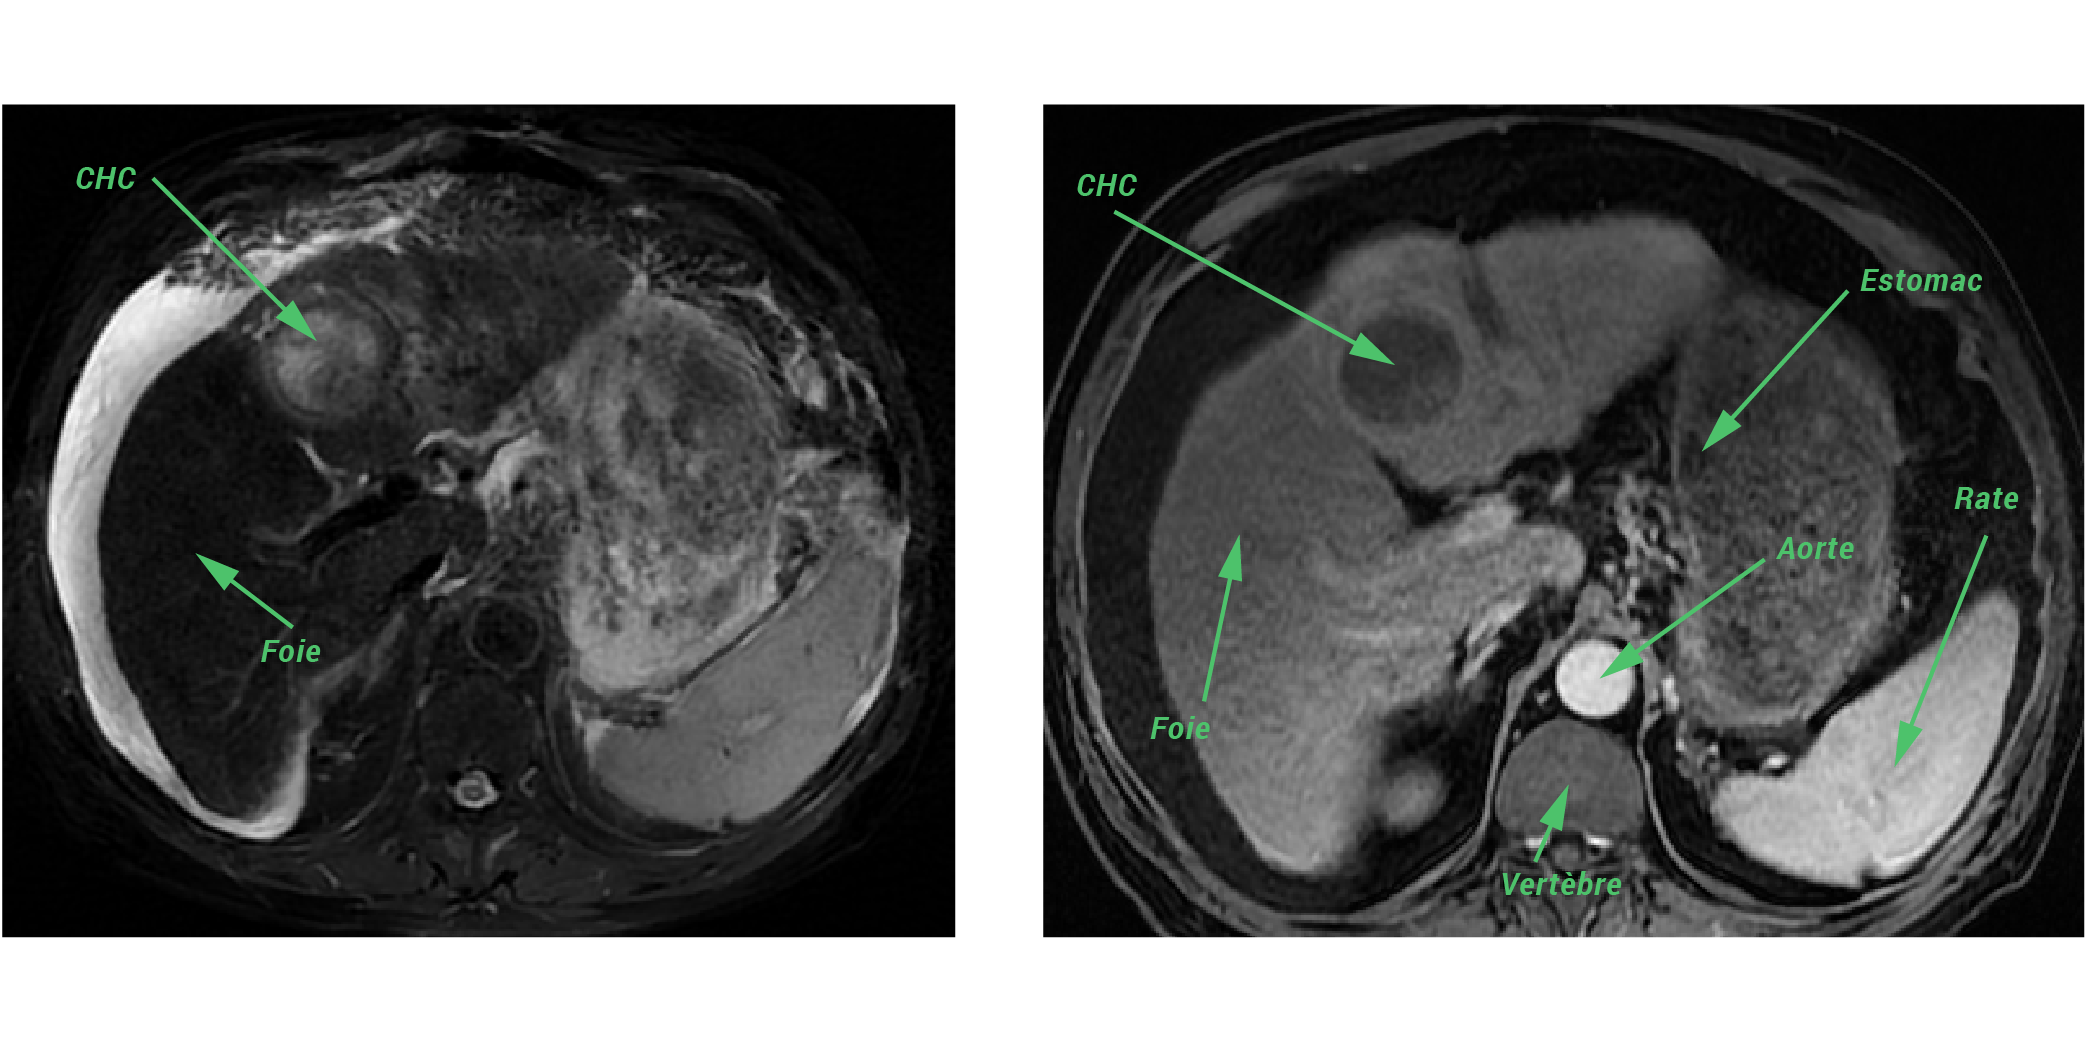

Τα τελευταία χρόνια έχει παρατηρηθεί αύξηση της συχνότητας των τυχαία ανακαλυπτόμενων βλαβών του ήπατος και των χοληφόρων, λόγω της αυξανόμενης χρήσης απεικονιστικών μεθόδων.

Η πλειονότητα των βλαβών ...